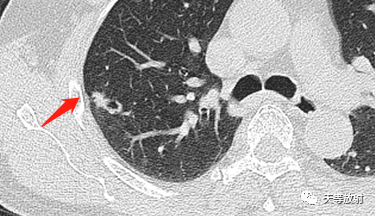

右肺上叶结节影,周围更小结节,形态不规则,胸膜面相对干净。